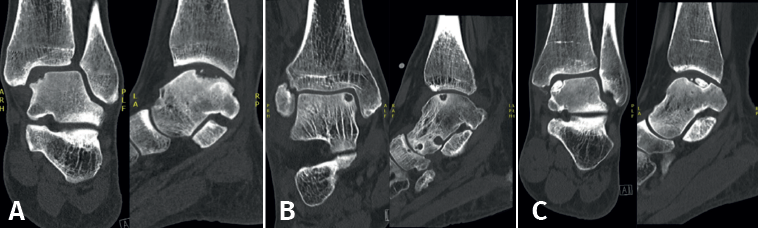

Fixation techniques have shown clinical and radiological success in 8 out of 10 patients, also maintaining their success in the long term (Figures 5 and 6). As these techniques preserve the hyaline cartilage and provide superior healing of the subchondral bone, they are advantageous over other surgical treatment options for OLTs, when feasible(39,41).

For acute displaced fragmentary lesions, fixation should be considered as the initial treatment(4). This should be performed as soon as possible to maximize healing potential and avoid further intra-articular damage(39). For chronic lesions, fixation can be applied when non-operative management is unsuccessful. As fixation techniques can provide superior subchondral bone healing(41), as well as preserving the overlying hyaline cartilage, it should be considered as the primary surgical treatment option when feasible.

Several fixation techniques using different materials have been described, including Kirschner wires, metal screws, bio-absorbable screws, bone pegs and/or fibrin glue(42,43,44,45). Fixation techniques may be performed arthroscopically when technically possible. The less invasive nature of arthroscopic fixation is theoretically advantageous. The most decisive factor for the possibility of arthroscopic fixation being the location/accessibility of the lesion. To achieve an adequate and stable fixation, the fragment needs to be fixated perpendicular to the talar dome. Therefore, the lesion must be located relatively anterior on the talar dome for arthroscopic fixation to be feasible(11). If arthroscopic fixation is not technically possible, it can also be performed as an open technique.

One specific surgical fixation technique is the Lift, Drill, Fill and Fix (LDFF) procedure(45). In this technique, the osteochondral lesion is visualized, and a beaver knife is used to create a flap. The flap is then lifted to allow for debridement and microfracturing of the subchondral bone. Cancellous bone, typically harvested from the distal tibial metaphysis, can be placed in the bed of the flap. Finally, the osteochondral flap is repositioned and fixed using bio-absorbable compression screws, chondral darts or bone pegs.